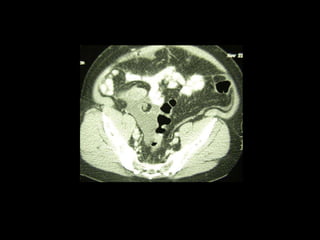

Pseudomyxoma peritonei (PMP) is a rare condition characterized by gelatinous ascites resulting from the rupture of appendiceal mucinous tumors, leading to significant abdominal complications. The incidence is approximately 2 cases per million per year, with a predominance in females, and diagnosis often relies on imaging techniques like ultrasound and CT scans. Effective treatment involves cytoreductive surgery combined with hyperthermic intraperitoneal chemotherapy (HIPEC) to manage disease progression and improve outcomes.